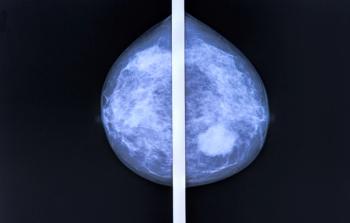

A City of Hope expert underscores the benefit of using antibody-drug conjugates, CDK4/6 inhibitors, PARP inhibitors, and checkpoint blockade in early-stage and metastatic breast cancer.

CDK4/6 inhibitors have demonstrated promise in treating patients with estrogen receptor (ER)–positive, HER2-negative breast cancer in both a neoadjuvant and adjuvant setting.